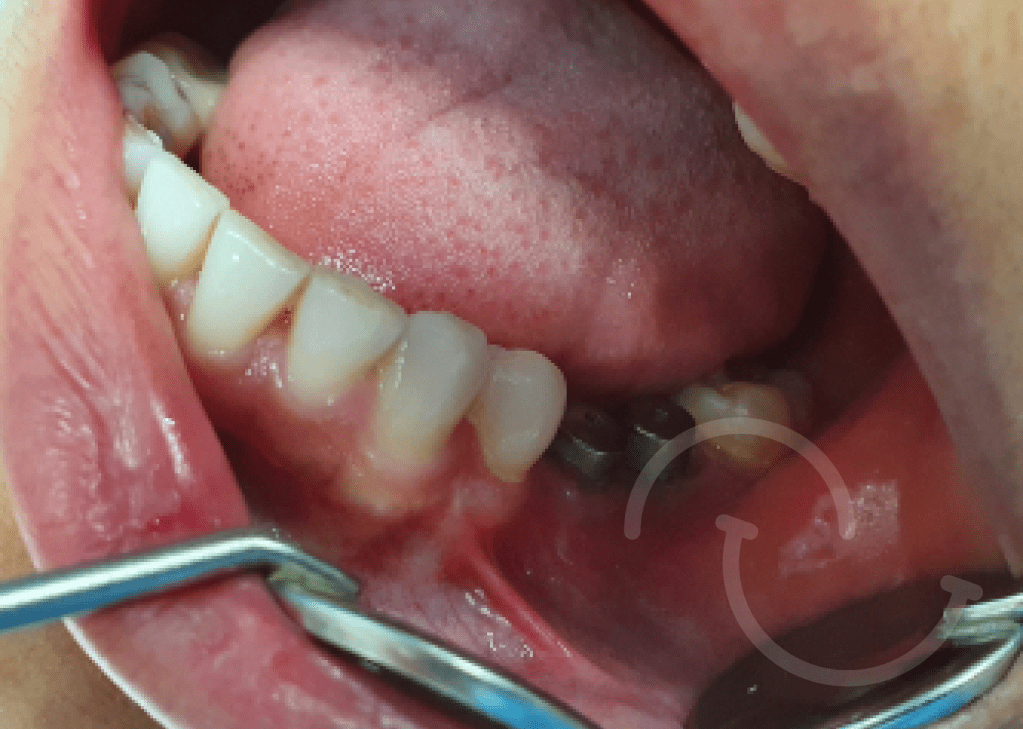

Caso expansion Osea

Casos de regeneración ósea vertical y horizontal con membrana Cytoplast